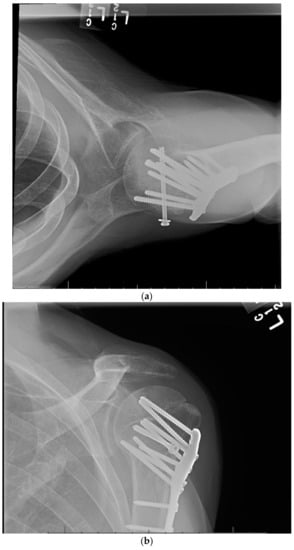

11. Open Reduction Internal Fixation with an Intramedullary Nail

12. Surgical Approach for ORIF with an Intramedullary Nail